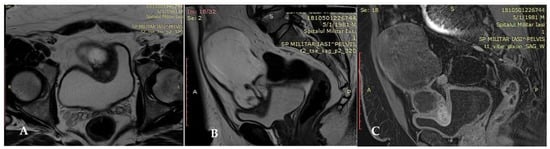

The patient’s urinary symptoms were relieved, abdominal drainage was removed on the sixth day and he was discharged on the 7th postoperative day after an uneventful stay. The urethral catheter was removed after 21 days and no complications were recorded after the patient’s release. The patient was subsequently referred to a medical oncologist who decided to perform periodic imaging evaluation without further adjuvant treatment. The patient was evaluated by thoraco-abdomino-pelvic computer tomography after 3 months from surgery. The scan did not identify any signs of local recurrence or pathological lymphadenopathies (Figure 5).

Figure 5.

CT examination revealed no local tumoral recurrence or adenopathies.